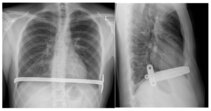

Abb. 5: Röntgenseit- und Röntgenfrontaufnahme eines Patienten nach minimal-invasiver Trichterbrustkorrektur. Der eingebrachte Metallbügel hält das Brustbein in der korrigierten Position.

- Minimal-invasive Trichterbrustkorrektur (nach Nuss): Die minimal-invasive Trichterbrustkorrektur nach Nuss ist mittlerweile die bei Trichterbrust am weitest verbreitete Operationsmethode. Idealer Operationszeitpunkt ist nach Abschluss des Längenwachstums, also in einem Alter zwischen 16 und 20 Jahren. Aber auch deutlich ältere Patienten können noch mit dieser Methode operiert werden. Bei der Operation wird mit Hilfe einer Brustkorbspiegelung ein U-förmiger, dem Brustkorb angepasster, kräftiger Bügel unter den Trichterboden des Brustbeins geschoben und seitlich an den Rippen fixiert. Das Brustbein wird durch den Bügel angehoben und in Normalstellung gehalten. Manchmal, insbesondere bei älteren Patienten, muss noch ein zweiter Bügel eingebracht werden. Ein entscheidender Vorteil dieser Methode ist, dass an Knochen und Knorpel selbst nicht operiert werden muss. Ein weiterer Vorteil ist, dass sich die Operationszugänge optisch weniger störend an der Seite des Brustkorbs befinden. Obwohl diese Operation minimal-invasiv durchgeführt wird ist meist eine längere und anfangs auch intensive Schmerztherapie zur Schmerzkontrolle erforderlich, da das Brustbein zurück in seine ursprüngliche Lage möchte und durch den kräftigen Bügel daran gehindert wird. Hinzu kommt, dass der Brustkorb aufgrund der Atembewegung ständig in Bewegung ist, so dass anfangs der Bügel gegen die Knochenhaut des Brustbeins reibt. Im Verlauf von Tagen bis Wochen nehmen diese Schmerzen meist kontinuierlich ab. Mit einem mehrtägigen Krankenhausaufenthalt und einer mehrwöchigen Arbeitsunfähigkeit muss allerdings gerechnet werden. 3 Jahre nach der Operation muss in einer zweiten Operation der Bügel wieder entfernt werde, der Brustkorb hat sich dann in aller Regel in der Normalstellung verfestigt. Die Bügelentfernung ist meist eine nur kleine und schmerzarme Operation und bedarf keiner langen Erholungsphase.